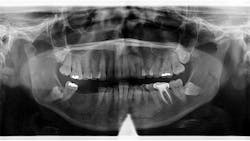

Patient: 50-year-old female

- 3 cm x 1.5 cm almost-vague radiodense lesion on lower left side around the apices of nos. 20-22

- Nonpalpable lesion

- Area not tender to palpation

- Patient taking prescription medication for an infection